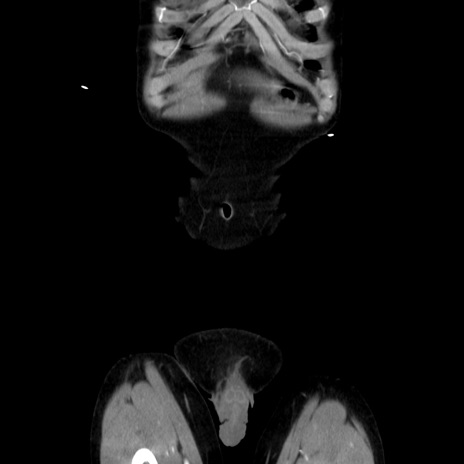

症例37(冠状断像)

【症例】40歳代 男性

【主訴】腹痛

【現病歴】4時間ほど前に電車に乗車中に臍部上より腹痛出現。徐々に増悪し起立困難となり、救急外来受診。生ものは数日食べていない。今朝お雑煮を食べた。

【身体所見】BT 36.8℃、BP 117/84mmHg、HR 91/min、SpO2 97%、苦悶様、腹部:臍上部広範囲圧痛あり、反跳痛±

【データ】WBC 8100、CRP 0.03